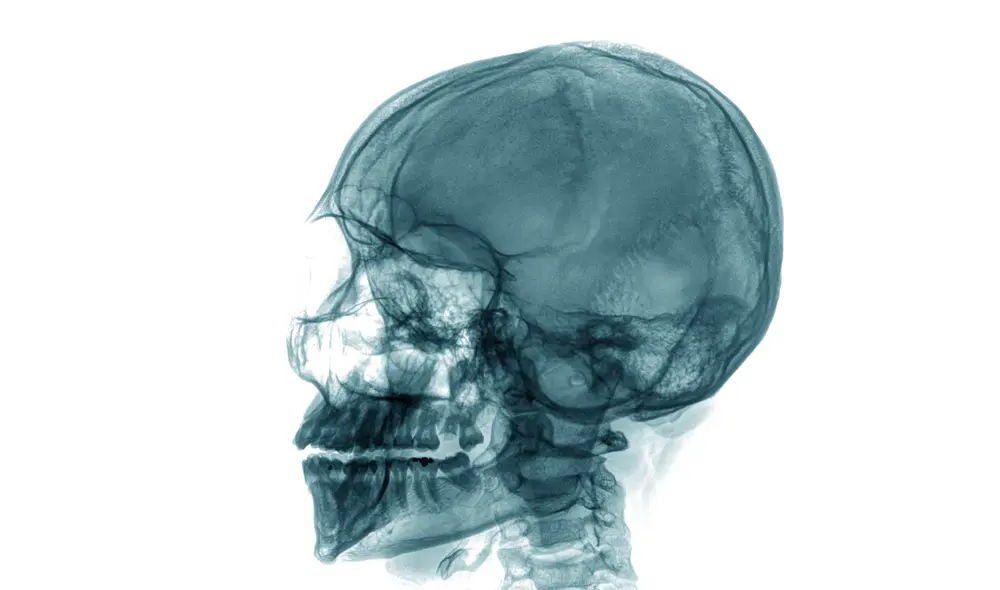

Los textos de anatomía describen que el músculo masetero, cuya fuerza de hasta 90 kg permite la masticación de los alimentos, consta de una capa superficial y otra profunda. Sin embargo, investigadores de los departamentos de Medicina y Salud Bucal de la Universidad de Basilea (Suiza) han mostrado la evidencia de una tercera capa nunca antes vista

“Esta sección profunda del músculo masetero se distingue claramente de las otras dos capas en términos de su curso y función”, expresó la Dra. Szilvia Mezey, una de las autoras principales del manuscrito publicado en la revista Annals of Anatomy.

Por la disposición de las fibras musculares, comentó Mezey, se sugiere que esta tercera porción se relaciona a la estabilidad de la mandíbula inferior del cráneo humano al elevarse y caer cuando se está usando el proceso coronoide o apófisis coronoide, dos protuberancias triangulares conectadas a los bordes mandibulares superiores.

“También parece ser la única parte del masetero que puede tirar de la mandíbula inferior hacia atrás, es decir, hacia la oreja”, agregó la experta en un comunicado de la mencionada casa de estudios.

Disección del masetero. C = parte donde el masetero se eleva y decae; S = parte superficial del músculo; D = zona profunda; T = músculo temporal (de masticación). Foto: Jens. C. Türp, Universidad de Basilea / UZB

Según los apuntes del artículo, para llegar a estas conclusiones, los expertos tuvieron que practicar disecciones macroscópicas en 12 cadáveres (siente hombres y cinco mujeres con un rango de entre 65 y 71 años). Ellos habían firmado un consentimiento para donar sus cuerpos con fines científicos.

Después, prosiguiendo con el análisis anatómico, obtuvieron imágenes de “16 cadáveres frescos” (cuatro hombres y 12 mujeres con un rango de edad que fluctuaba entre los 66 y 95 años).

Cuando quisieron detallar más las observaciones, la serie de imágenes se convirtieron en reconstrucciones 3D. También se aplicó una resonancia magnética en el cuerpo fallecido de una mujer de 40 años. De la misma forma, detectaron la tercera capa del músculo masetero.

“El conocimiento preciso de la arquitectura del músculo masetero también puede ser importante en un contexto clínico, con respecto al tratamiento de trastornos temporomandibulares o intervenciones quirúrgicas en la región del arco cigomático (estructura ósea de los lados de la cara, arriba de los conductos auditivos, donde se insertan varios músculos)”, concluyeron los investigadores.